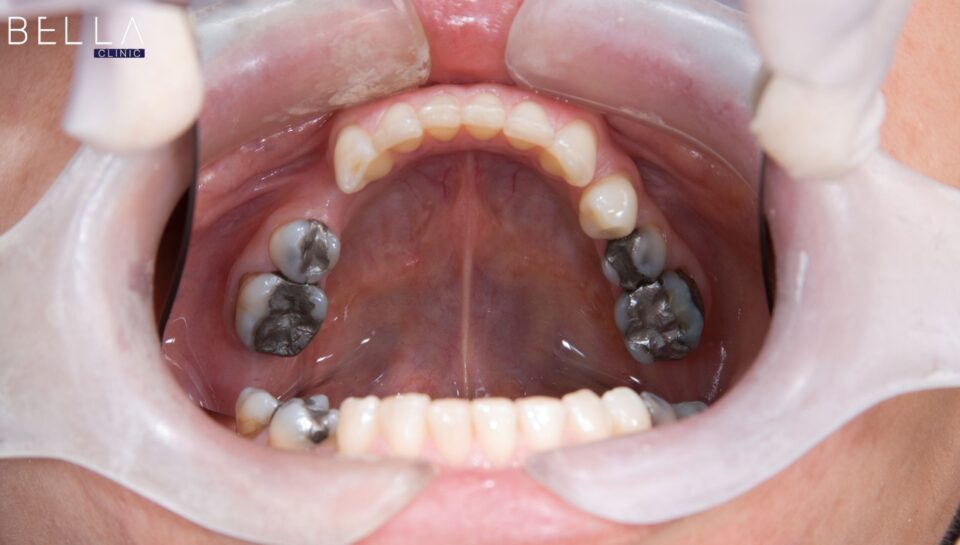

بالإضافة إلى ذلك، تفشل الحشوات التجميلية البسيطة غالباً في علاج المشاكل المعقدة بشكل مستهدف وفعال تماماً. بناءً على ذلك، يقدم التدخل الطبي دفعة قوية وضرورية لتغيير مظهرك الخارجي بالكامل وإبراز نضارتك الدفينة.

من ناحية أخرى، تعالج هذه الخطوة حالات كسر وضعف المينا المرتبطة بالتسوس العميق بفاعلية وأمان لتجنب المضاعفات. نتيجة لذلك، يحسن التدخل الطبي مظهر الثلث السفلي للوجه ويزيد من راحتك النفسية بشكل جذري وملحوظ جداً.

ثالثاً، يفضل بعض الأطباء استخدام التركيبات الخزفية الكاملة للحالات التي تتطلب قوة استثنائية وتجميلاً مثالياً. يبرد الطبيب السن التالف ويركب الغطاء الزيركوني بمهارة فائقة لتعويض الجزء المفقود بالكامل وبأمان تام.

علاوة على ذلك، يضمن هذا التدخل السريع التخلص من الفراغات المزعجة بشكل نهائي ومستقر للمريض تماماً. هكذا يحقق المريض تحولاً جذرياً وشاملاً يعيد له قدرة المضغ بقوة ووضوح ومظهر طبيعي.